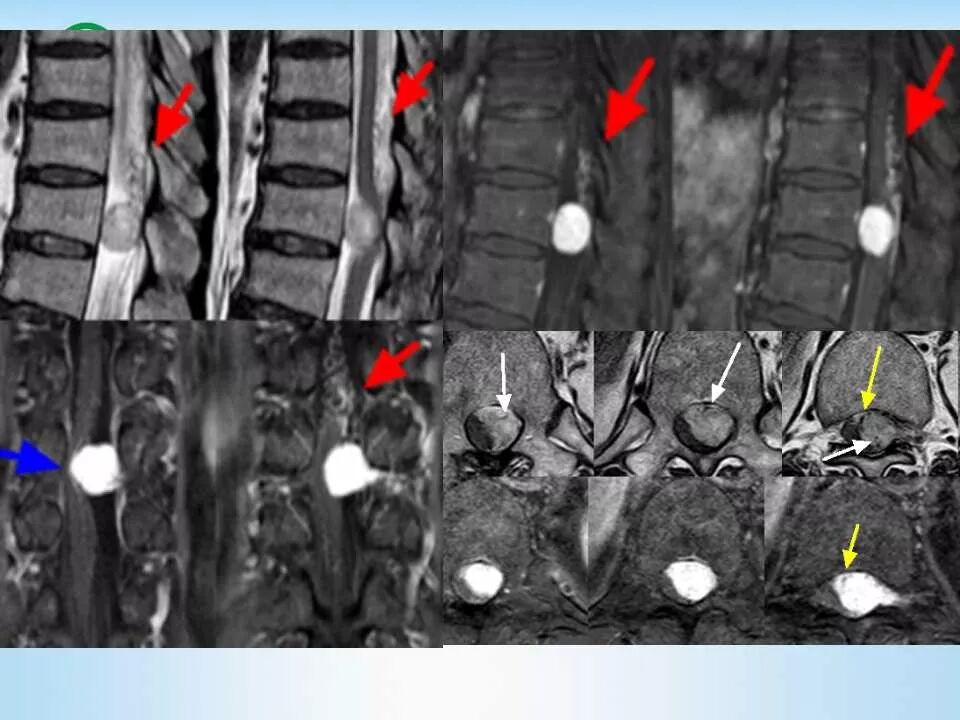

北方影像联盟 一周病例精选之“椎管占位”